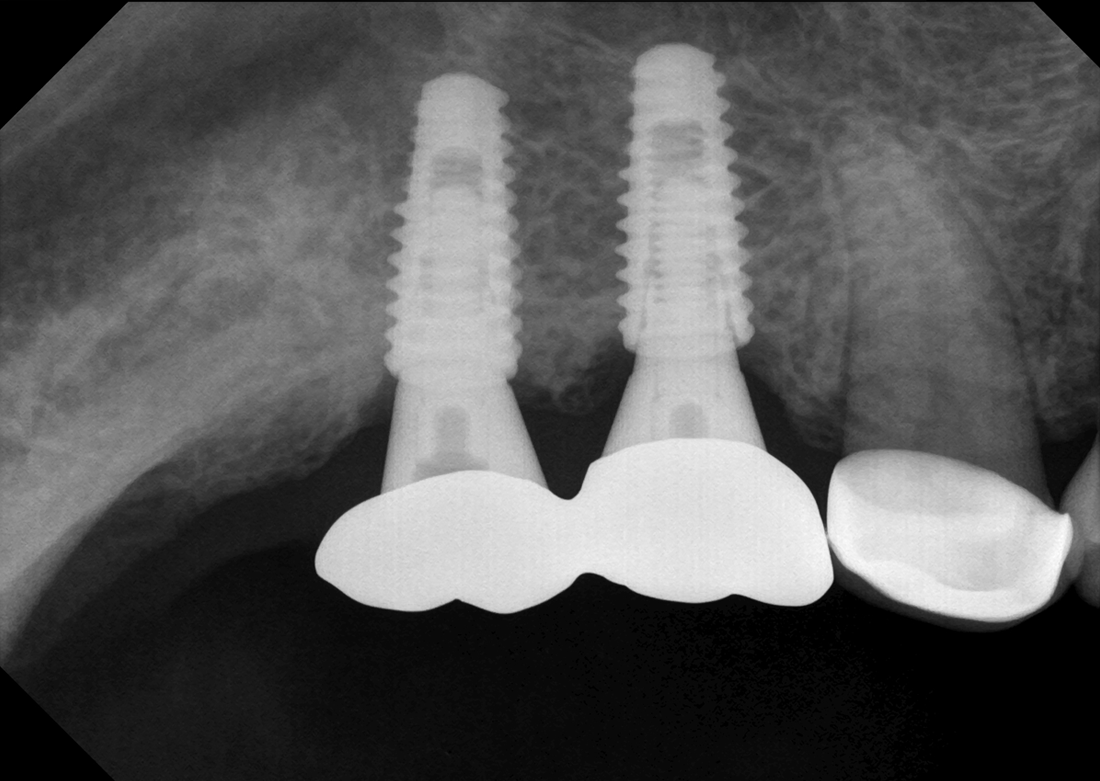

KLIMIKAI FELVÉTELEK

Hosszú tapasztalat során felhalmozott szakértelmünkkel kiváló diagnosztikai képeket biztosítunk.

Ez a Genoray büszkesége, amelyet világszerte szeretnek.